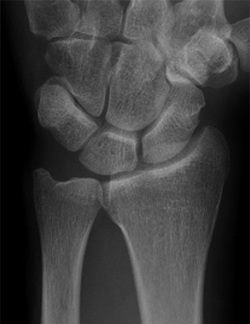

【正常な手関節X線像】

正面像

側面像